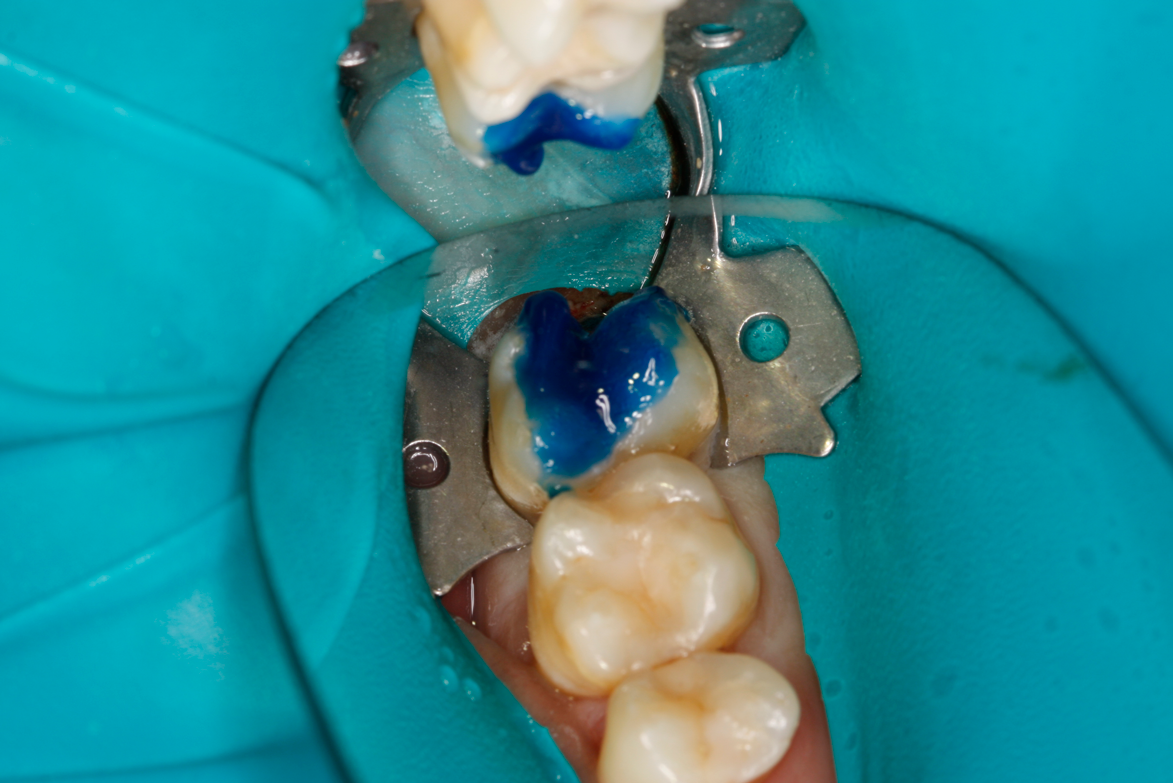

Figure 8A is a radiograph revealing deep root caries previously restored temporarily by a resident at the AEGD Residency Program clinic with glass ionomer utilizing a lateral rather than occlusal approach. After the glass ionomer failed to adhere, another resident again attempted a lateral approach that resulted in the restoration shown in Figure 8B. A third resident had success with an occlusal approach, removing a failed occlusal composite to access the distal  (Figure 9). This attempt was successful both in the preparation of the lesion and in the placement of a dual- cure bulk-fill flowable (Bulk EZ Plus, Zest Dental Solutions; alternatively: HyperFIL®, Parkell; Fill-Up!, Coltene) extruded through a bendable needle (Figure 10). Figure 11 shows the final preparation after tissue removal was accomplished with rotary gingitage; note that this was performed with the rubber dam in place. An air abrasion device (Groman Etchmaster, Groman Dental; alternatively: PrepStart H2O, Zest Dental Solutions; Bioclear Blaster, Bioclear) was used with potassium bicarbonate to remove biofilm prior to acid etching (Figure 12). Phosphoric acid 37% was utilized in a total etch fashion (Fig- ure 13 and Figure 14) for 20 seconds. Figure 15 shows the universal bond (Scotchbond Universal, 3M; alternatively: All-Bond Universal®, BISCO; Prelude One, Danville Materials) with metha- cryloyloxydecyl dihydrogen phosphate (MDP) being scrubbed into the cavity for 20 seconds. After air thinning for 20 seconds, the adhesive was light cured for 40 seconds at 1,200 mw/cm2power density (Figure 16).

Fig 10. Occlusal approach was successful in the placement of a dual-cured bulk-fill flowable. Note the depth of box form.

Figure 10

Fig 11. Final preparation after gingitage with coarse diamond bur to remove soft tissue from the cavity in tooth No. 2.